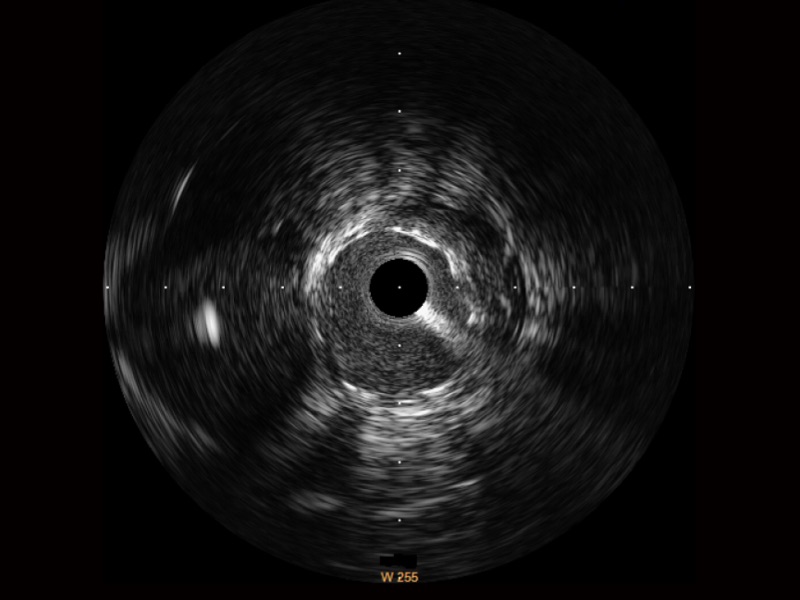

血管内超声(IVUS) 通过对病变程度、性质和累及范围的精确判断,可帮助选择治疗策略和方法,指导介入治疗过程,能够降低主要不良心血管事件,改善预后,在复杂病变介入治疗中用于指导支架置入的优势更为明显。血管内超声(IVUS)已成为精准心血管介入治疗的“金标准”。

乐玩lewin国际始终关注未满足的临床需求:超宽频成像技术同时提供高清分辨力和充足穿透深度,适应不同血管结构的治疗引导;智慧赋能,简化操作,降低临床应用难度和缩短学习曲线。